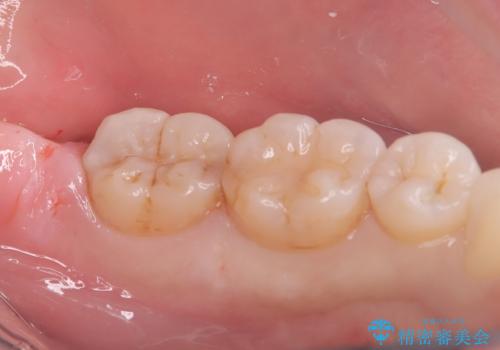

来院時、右下7遠心9mm、舌側6mmと深い歯周ポケットを認めました。

遠心から舌側、唇側に及ぶ深い垂直的骨欠損も認めたため、歯科衛生士による歯周基本治療の後、歯周外科(再生療法)を行いました。

レントゲン写真は、処置後一年経過時のもので、歯周ポケットは遠心4mm、舌側3mmまで減少、出血なし。